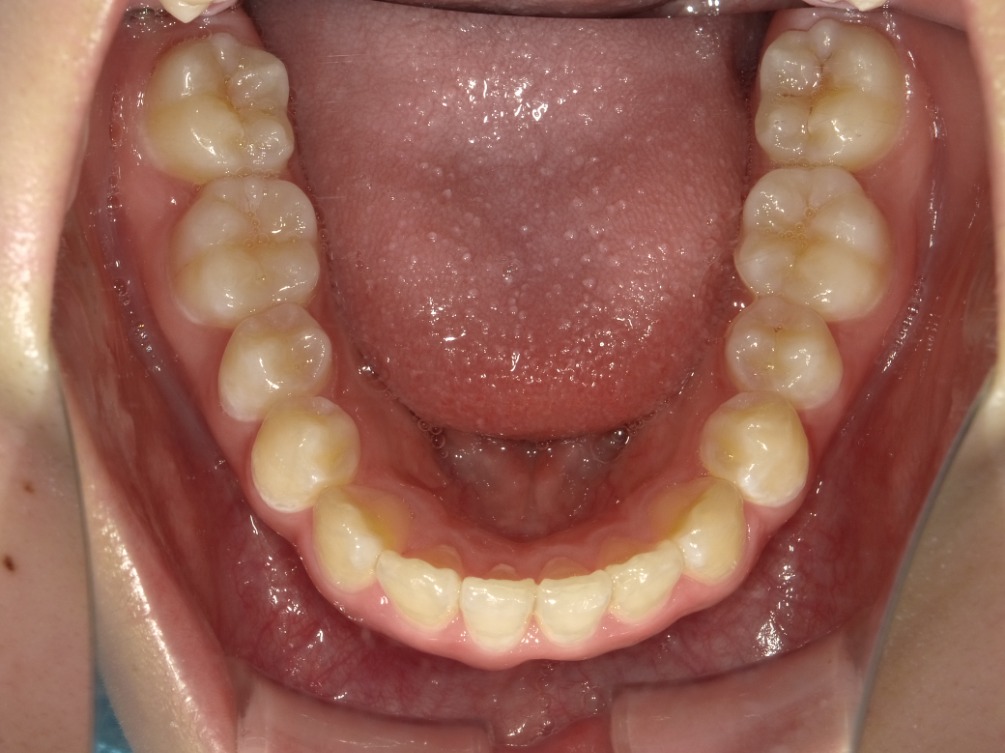

• BEFORE

症例集 インビザライン 下顎

矢印

AFTER

下顎